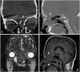

Meningoencephalocele

Encephalocele is a neural tube defect characterized by sac-like protrusions of the brain and the membranes that cover it through openings in the skull. These defects are caused by failure of the neural tube to close completely during fetal development. [Source: Wikipedia ]